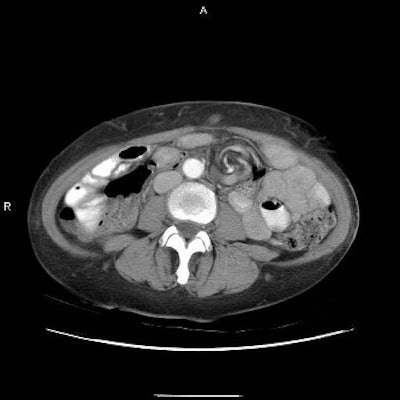

Both UGI and CT detect signs signaling adhesion or internal hernia, such as dilated bowel segments and a transition from dilated to collapsed bowel. But only CT depicts classic signs of internal hernia such as crowding, stretching, and engorgement of mesenteric vessels.

Three images show internal hernia following Roux-en-Y gastric bypass. The CT scans (top, middle) and small bowel study (below) show a cluster of mildly dilated bowel segments in the left abdomen, with a crowded, twisted appearance of the bowel and mesenteric vessels. Images courtesy of Dr. Michael Federle.